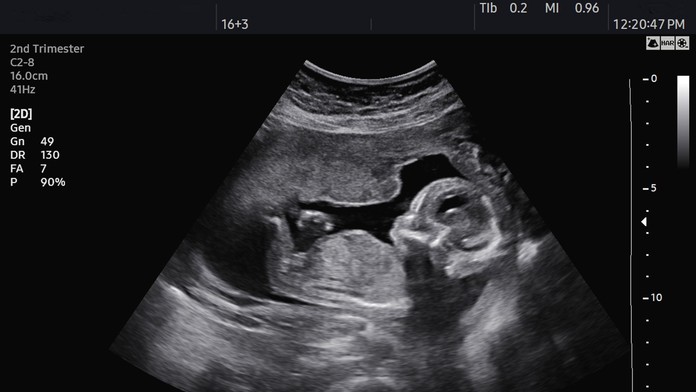

V 20. týždni vykonal tím 15 lekárov v nemocnici Johna Radcliffa v Oxforde päťhodinovú operáciu, pri ktorej odstránili rakovinové bunky na oboch vaječníkoch za maternicou.

Tú vybrali z tela no nechali ju napojenú na maternicovú tepnu. Orgán bol počas zákroku celý čas zabalený do teplého sterilného obalu s fyziologickým roztokom, čím imitovali prostredie v tele.

Dvojica lekárov každých 20 minút menila zábal, aby udržala dostatočnú teplotu. Po tom, ako chirurg odstránil nádor, vložili maternicu späť.